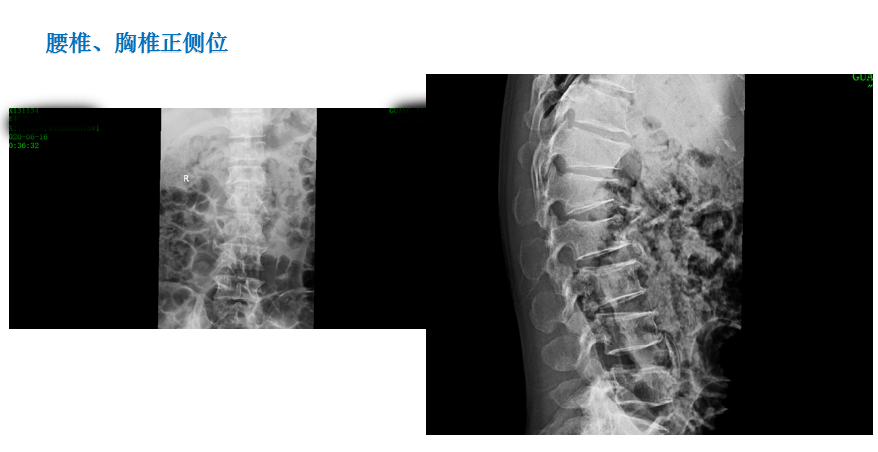

患 者:李某,男,42岁。

主 诉:因摔伤致腰背部、右跟部疼痛伴活动受限2小时,入院治疗。

症 见:患者从2米高处摔下,双足着地,即觉腰背部、右跟部疼痛伴活动受限,受伤当时无胸闷气促,无恶心呕吐。

专科检查:胸腰椎稍后突,胸腰部稍肿胀,无瘀青,皮肤黏膜完整,腰1、2棘突处轻压痛,腰2椎旁轻压痛,局部叩痛,双侧沿坐骨神经区无压痛,右大腿前中部感觉减退。双大腿内侧、内踝、第3跖趾关节背侧、足跟外侧感觉无减退。肛门反射存在,双侧膝反射、双侧踝反射消失。髂腰肌肌力(Ⅴ级)。双侧股四头肌肌力(Ⅴ级),双侧胫骨前肌肌力(Ⅴ级),双侧踇长伸肌肌力(Ⅴ级),双侧踇长屈肌肌力(Ⅴ级),双侧踝关节跖屈(小腿三头肌)肌力(Ⅴ级)。直腿抬高试验(-)、加强试验(-),拾物试验(不能配合完成)。腹壁反射、肛门反射正常。右肾区叩击痛(+),左肾区叩击痛(-),输尿管移行区无叩击痛。左髋部叩击痛,髋关节活动可,4字征(-)。右外踝、跟部肿胀,皮肤黏膜完整,局部可见皮下淤血,压痛,未触及骨擦感,足背动脉可及,右足末梢感觉无减退,右踝外侧应力试验、抽屉试验不能配合,右踝关节主动活动稍受限,右足各趾活动可。

影像资料:

诊 断:

1:腰1、2椎体压缩骨折(椎体分别压缩约40%、10%);

2:腰椎退行性改变伴椎管狭窄;

3:腰3/4、4/5、腰5/骶1椎间盘膨出;

4:右跟骨骨折;

5:胸12陈旧性骨折。